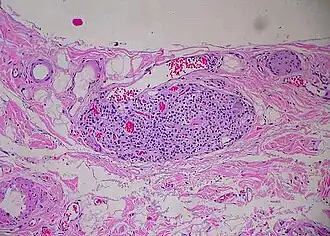

Paraganglion of gallbladder | |

A paraganglion (pl. paraganglia) is a group of non-neuronal cells derived of the neural crest. They are named for being generally in close proximity to sympathetic ganglia. They are essentially of two types: (1) chromaffin or sympathetic paraganglia made of chromaffin cells and (2) nonchromaffin or parasympathetic paraganglia made of glomus cells. They are neuroendocrine cells, the former with primary endocrine functions and the latter with primary chemoreceptor functions.[1]